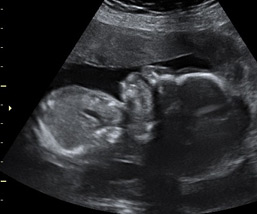

Ecografías de la semana 28 de embarazo

Ecografía semana 28: cara de perfil. Podemos observar el perfil del bebé y el tórax, que se visualiza a la izquierda de la ecografía. La placenta está situada en la parte superior de la imagen.